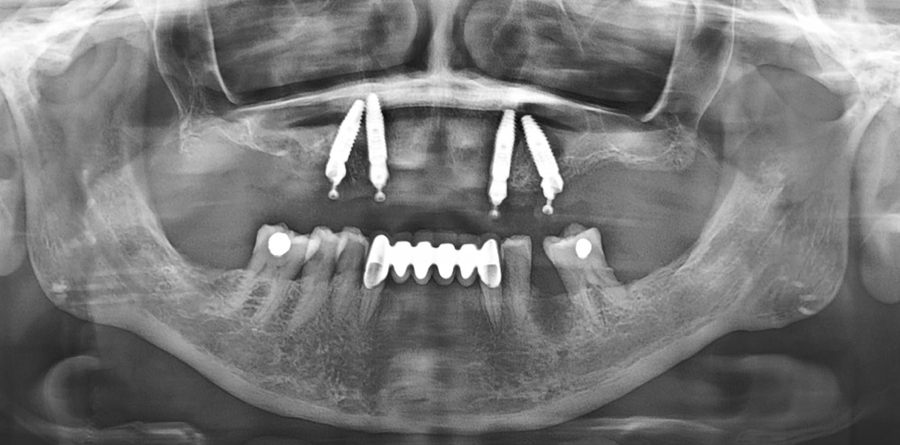

Vorher Nachher